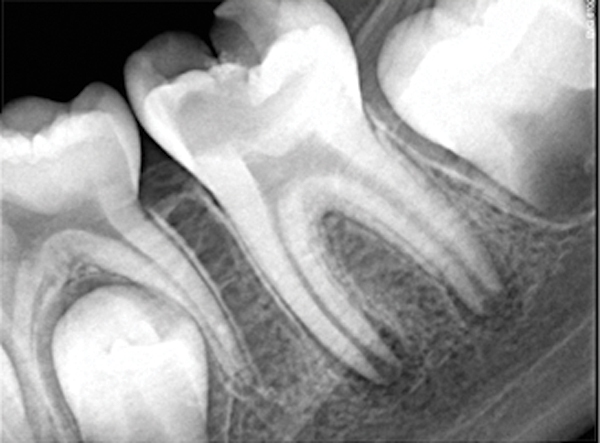

Fig 11. Preoperative radiograph. Courtesy of Dr. Guillaume Jouanny.

Figure 11

Fig 12. Postoperative radiography after full pulpotomy was performed. Courtesy of Dr. Guillaume Jouanny.

Figure 12

Case 2: Pulpotomy

In this case, the tooth tested vital but showed clinical signs of irreversible pulpitis. Treatment with a full pulpotomy was chosen to improve the chances the remaining pulp would survive and remain healthy. The preoperative radiograph in Figure 11 shows extensive caries in the tooth and a slightly widened apical periodontal ligament. A full pulpotomy was performed using the BC putty (Figure 12). After the putty set, a coronal restoration was placed, and an immediate postoperative radiograph was taken and viewed. At the 1-year follow-up, the tooth was asymptomatic, and the radiograph showed continued root development (Figure 13), a healthy apical periodontium, and, importantly, no calcifications in the remaining pulp (as is often seen with a calcium hydroxide therapy). A radiograph taken of the contra-lateral tooth showed similar root development (Figure 14).